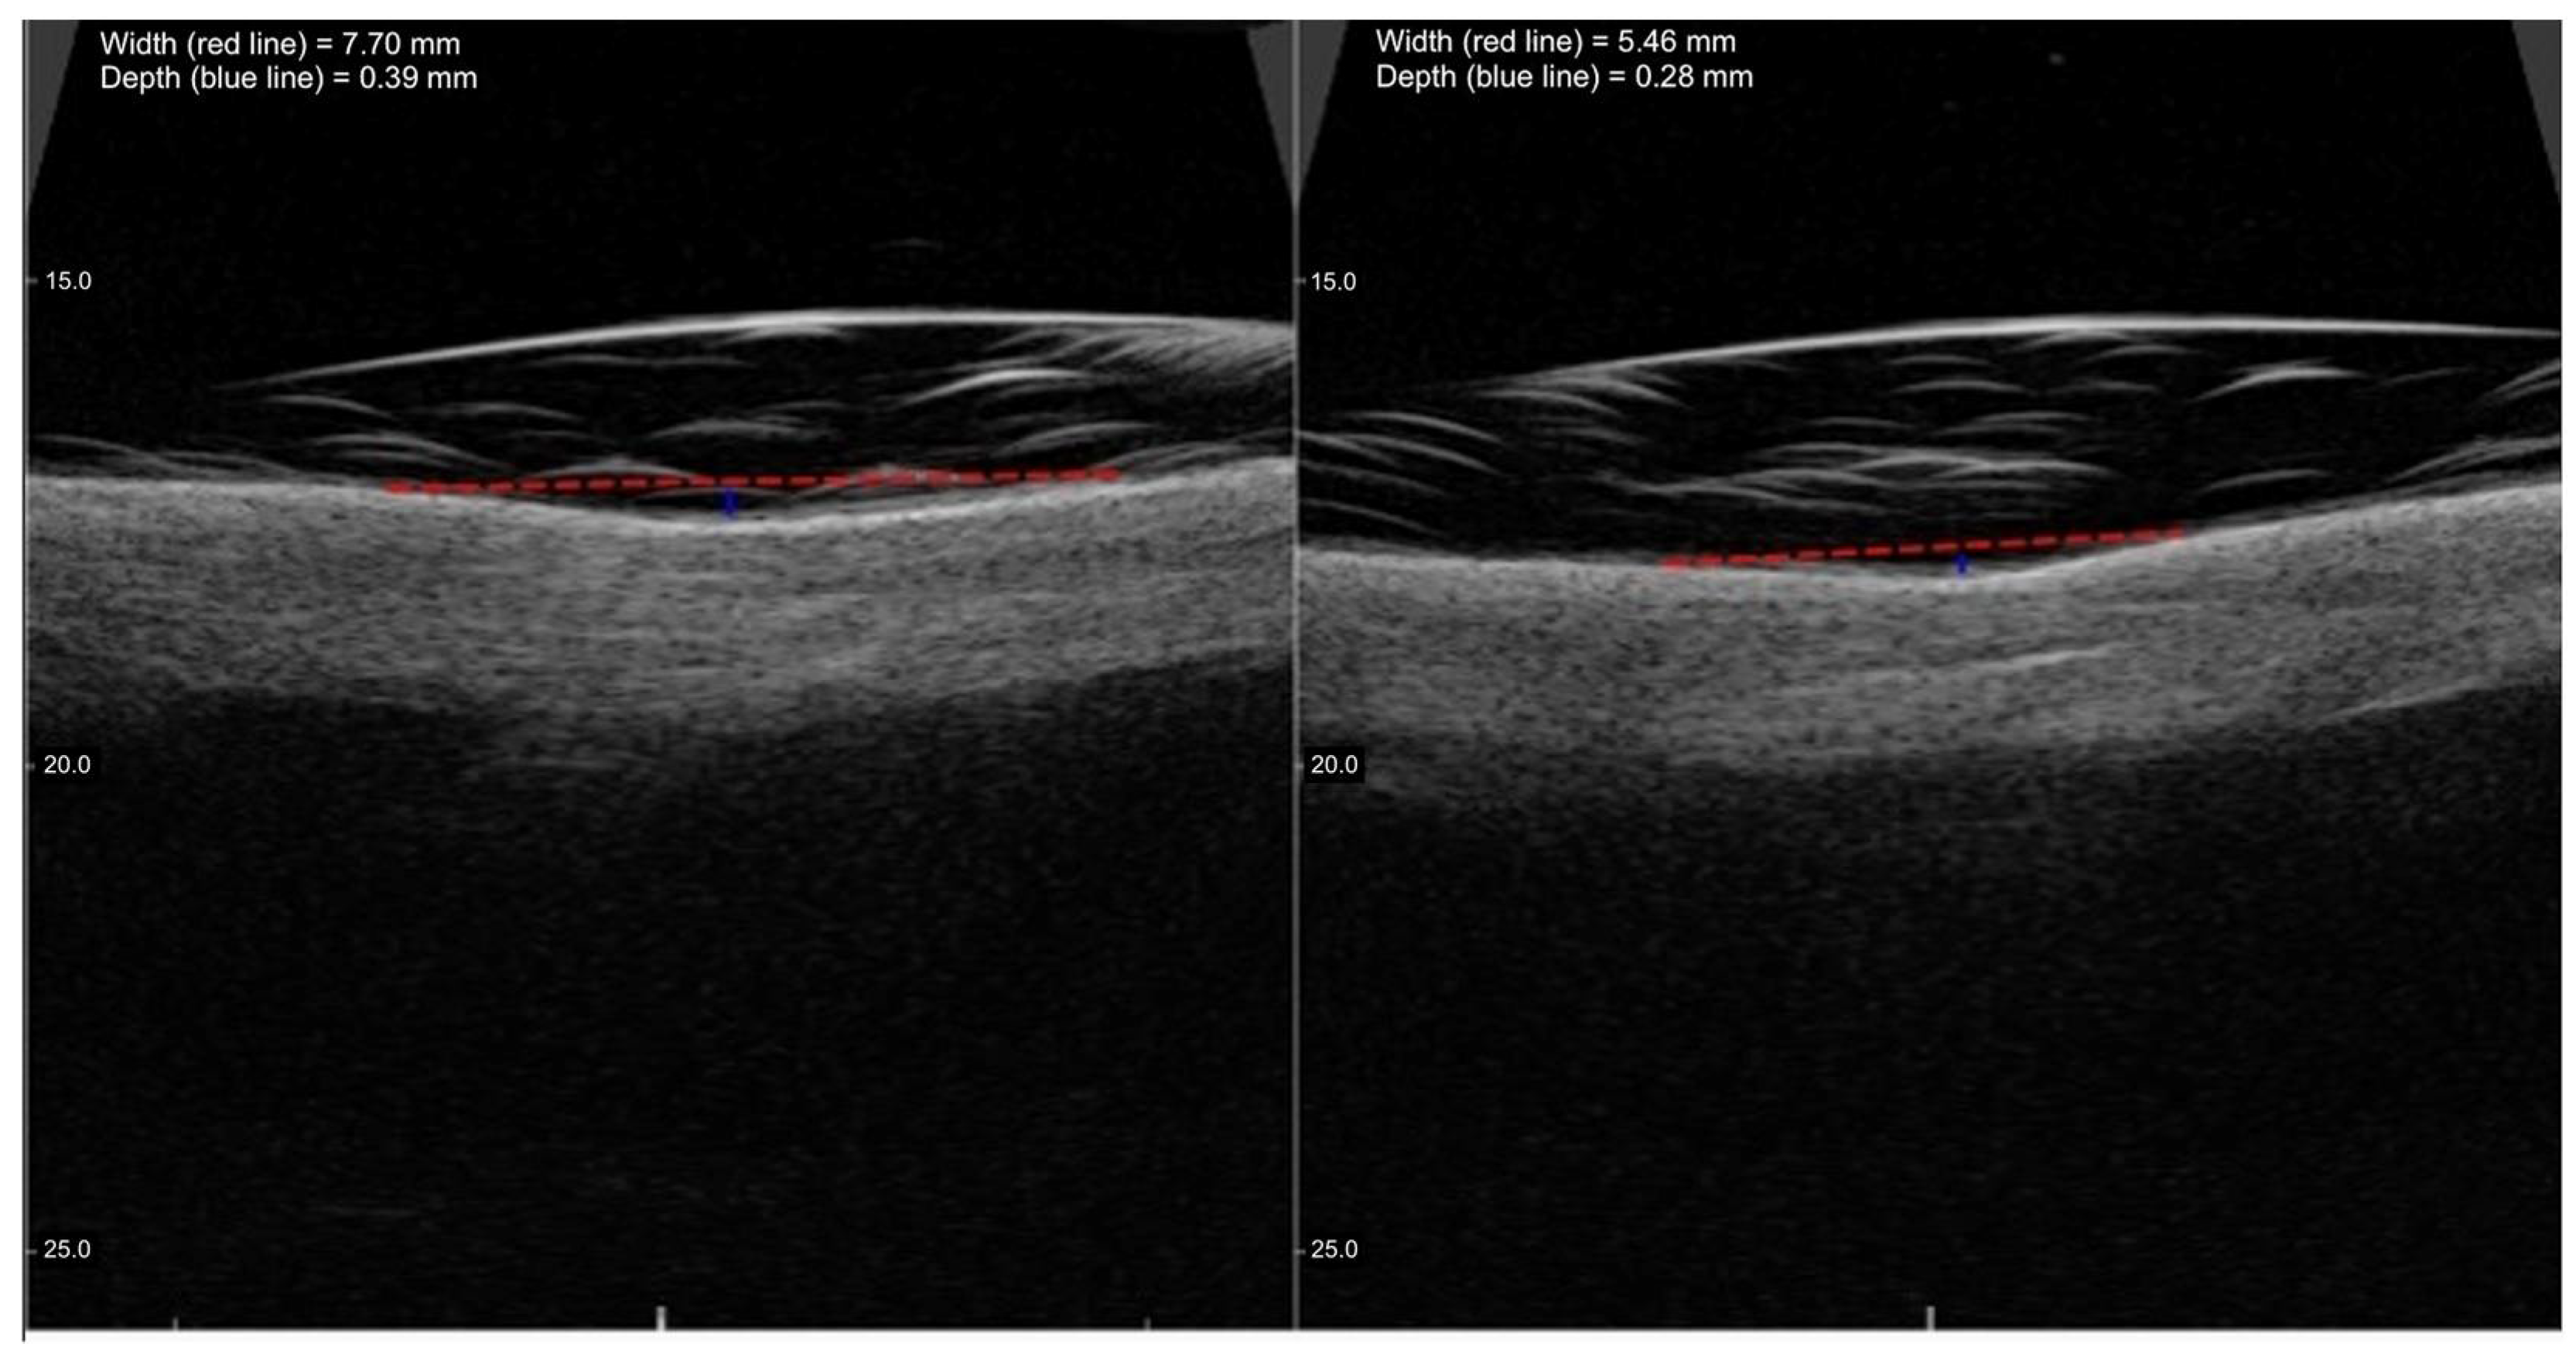

These results display a statistically significant reduction in both SD depth and SD width, as detailed in Table 2. Figure 5 presents the methodology and the treatment effects regarding SD width and depth reduction before and after the procedure evaluated with high-frequency ultrasound.

Figure 5.

Representative high-frequency ultrasound images showing the reduction in SD width and depth before and after 1470 nm non-ablative laser therapy. The left panel shows baseline evaluation, while the right panel corresponds to Day 118–132 post-treatment. A marked decrease in lesion depth and dermal indentation is visible, consistent with progressive tissue remodeling and clinical improvement. The blue line and the red line indicate the width and the depth of the SD lesion, respectively.